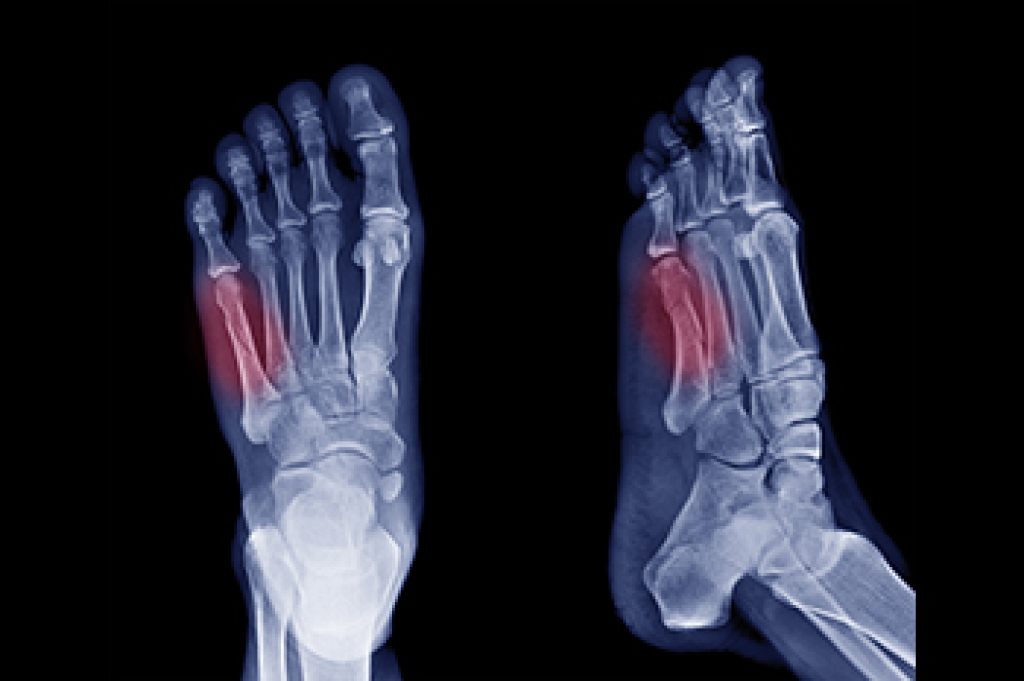

Among the array of foot injuries, a Jones fracture demands rigorous attention. A Jones fracture, or avulsion fracture, occurs when a tendon or ligament forcefully pulls a small piece of bone away from the main bone. In the case of a Jones fracture, this typically occurs in the fifth metatarsal bone, which connects the pinky toe to the rest of the foot. This type of injury is often the result of a significant and direct impact, causing intense pain. Pain at the base of the foot is a primary symptom and should never be ignored, even if other symptoms are absent. Additionally, impaired movement of the little toe is common, though complete immobility may not always happen. Neglecting these symptoms can worsen the injury and may lead to surgery if the bone does not heal properly. Other signs to watch for with a Jones fracture can include impaired balance, swelling around the fifth metatarsal joint, and bruising around the little toe. Prompt medical attention from a podiatrist, including X-rays for accurate diagnosis and appropriate treatment, is essential for effective healing and preventing long-term complications. If you suspect a Jones fracture or are experiencing any of these symptoms, it is suggested that you schedule an appointment with a podiatrist for proper evaluation and care.

A broken foot is caused by one of the bones in the foot typically breaking when bended, crushed, or stretched beyond its natural capabilities. Usually the location of the fracture indicates how the break occurred, whether it was through an object, fall, or any other type of injury.

Those that suspect they have a broken foot shoot seek urgent medical attention where a medical professional could diagnose the severity.

Treatment for broken bones varies depending on the cause, severity and location. Some will require the use of splints, casts or crutches while others could even involve surgery to repair the broken bones. Personal care includes the use of ice and keeping the foot stabilized and elevated.